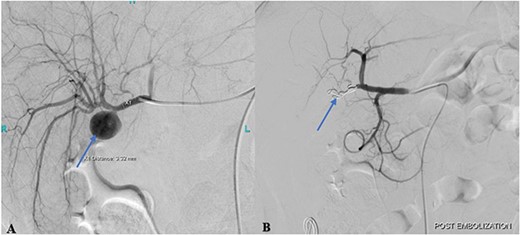

Cannulation of the celiac and superior mesenteric arteries were performed using a 4 French C1 Catheter to perform an angiogram. The angiogram showed a saccular aneurysm measuring 23 × 21 mm arising from the right hepatic artery just at the origin of the cystic artery stump (Fig. 2A). After considering multiple options, it was decided to embolize the hepatic artery proximal and distal to the aneurysm using the jail technique. Selective cannulation of the right hepatic artery was performed with a catheter tip placed distal to the origin of the aneurysm using a Progreat microcatheter. The distal segment was then embolized using three steel coils. The microcatheter was then retracted, proximal to the aneurysm origin followed by proximal segment embolization using three steel coils.

(A) Pre-embolization angiogram of the hepatic artery demonstrates pseudoaneurysm of the cystic artery stump (arrow). (B) Post-coil embolization angiogram of the hepatic artery shows no further filling of the pseudoaneurysm (arrow).